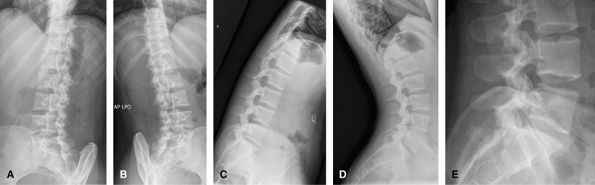

Lumbar Spine

The images vary from center to center. Some will include

an AP pelvis, others just AP and lateral lumbar spine. Good to assess

for acute trauma, alignment, spondylolysis, and spondylolisthesis. CT is

usually performed if trauma is seen on the radiographs. MRI is useful

in cases of radiculopathy.

![]() |

Figure 55 (A) AP pelvis. (B) AP lumbar spine. (C) Lateral lumbar spine.